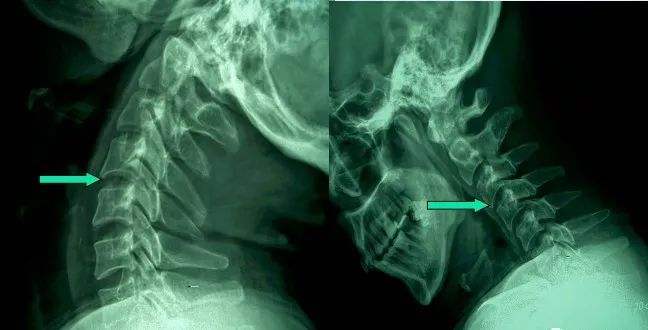

1、頸椎移位

由于頸椎關(guān)節(jié)突間關(guān)節(jié)面近乎水平位,一旦椎間盤發(fā)生退變、椎間隙即變窄,關(guān)節(jié)囊及韌帶松弛,加上頸部活動時重力的影響,即可造成積累性損傷,加速頸椎退變和不穩(wěn),導(dǎo)致頸椎關(guān)節(jié)發(fā)生移位,使椎間孔變狹,椎管徑發(fā)生改變,壓迫神經(jīng)根或脊髓,產(chǎn)生臨床癥狀與體征。